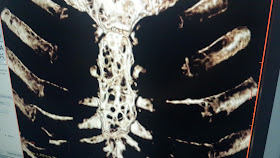

Se solicitó TAC

TAC: Ureter retrocavo